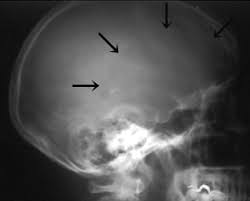

Paget's disease

- X-ray: osteoporosis circumscripta in skull is characteristic